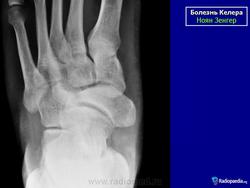

На рентгенограмме в начальной стадии выявляется легкий остеопороз, затем уплотнение костной структуры ядра окостенения ладьевидной кости (ядер окостенения может быть несколько). Появляется сплющивание и фрагментация ладьевидной кости, ее деформация в виде чечевицы или полумесяца. Прилежащие суставные щели расширяются.

Остеохондропатия ладьевидной кости стопы